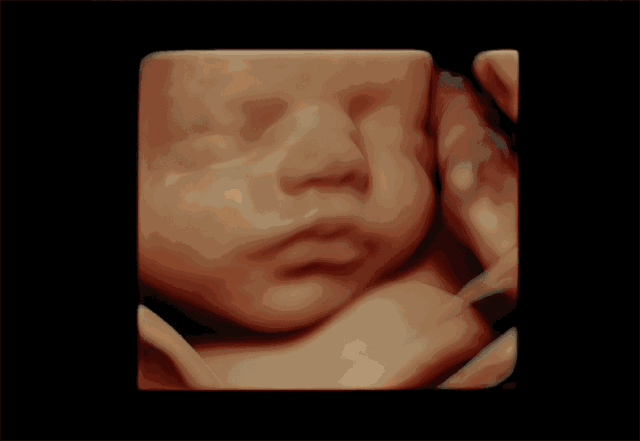

孕婦彩超是一種超聲檢查。除了一般的彩色超聲波功能外,還可以執(zhí)行胎兒頭部和臉部的立體成像。它可以清楚地顯示眼睛、鼻子、嘴巴、腹等狀況,并可以幫助醫(yī)生直接診斷胎兒先天性畸形,包括表面畸形,內(nèi)臟畸形和面部和面部畸形,可以確定胎兒在子宮中的確切位置。

四維彩色多普勒超聲在功能的基礎(chǔ)上還增加了時(shí)間維度參數(shù),并且可以實(shí)時(shí)觀察胎兒動(dòng)態(tài)的運(yùn)動(dòng)圖像,能夠更加清晰的篩查胎兒在子宮內(nèi)的狀態(tài),篩查胎兒是否有異常,提供準(zhǔn)確的科學(xué)依據(jù),及早發(fā)現(xiàn)、及早作出解決方案。

彩超是能夠監(jiān)測(cè)到胎寶寶的健康情況,其中四維彩超除了是準(zhǔn)媽媽和BB的“第一次”見面,還能夠看到ta在肚子里或活潑或文靜的可愛模樣,從而進(jìn)行重要的排畸檢查,所以也叫胎兒畸形篩查,是孕期特別重要的一次超聲檢查。